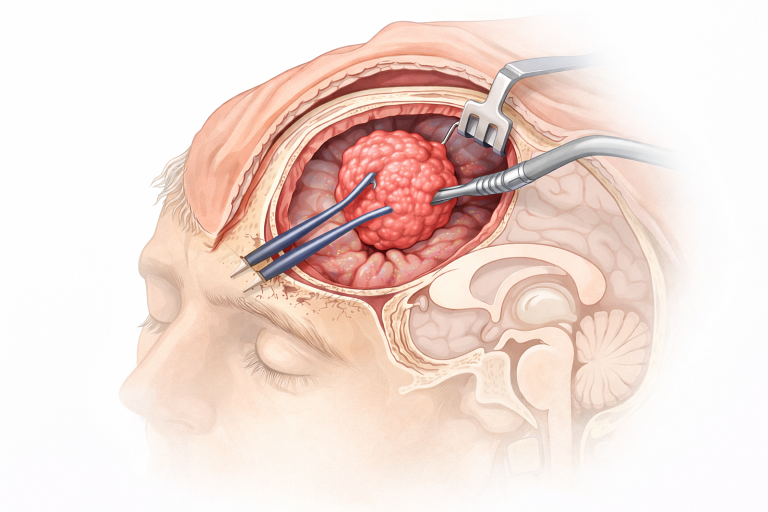

Tratamentul principal este rezecția chirurgicală, dar aceasta poate fi dificilă datorită proximității unor structuri critice (hipotalamus, chiasmă optică). Opțiunile chirurgicale includ:

- Rezecția totală: este ideală, dar riscantă, deoarece poate genera deficite neurologice și endocrine permanente.

- Rezecția subtotală sau parțială: mai frecvent realizată, urmată de radioterapie pentru a limita recurența.